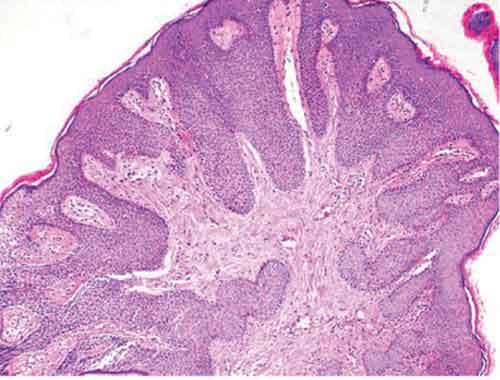

Anche le ragazze che non hanno ancora avuto rapporti sessuali sono a rischio infezione da Hpv, il papillomavirus, e sono piu’ a rischio di quanto si pensasse finora. A dirlo e’ un nuovo studio del Cincinnati Children’s Hospital pubblicato sulla rivista “Archives of Pediatric & Adolescent Medicine”. Quella da Hpv e’ una infezione che e’ soprattutto passata attraverso rapporti vaginali o anali. Tuttavia, puo’ essere anche contratta mediante contatti genitale-genitale o manuale-genitale. Si tratta di una malattia di solito temporanea ma che puo’ causare anche cancro alla cervice. I ricercatori hanno coinvolto 259 ragazze di eta’ compresa fra 13 e 21 anni che fra il 2008 e il 2010 avevano ricevuto la prima vaccinazione contro l’Hpv. La maggior parte erano afro-americane (78 per cento).

Fra le ragazze sessualmente attive, il 70 per cento e’ risultata positiva all’Hpv. Delle 69 ragazze che non avevano ancora avuto rapporti sessuali, 8 sono risultate positive all’Hpv, due delle quali all’Hpv-16, il ceppo a piu’ alto rischio. “Una percentuale maggiore di quanto ci si aspettasse, probabilmente dovuta al fatto che le ragazze avevano avuto altri tipi di esposizione sessuale”, ha commentato Eduardo Franco, della McGill University, non coinvolto nello studio. (AGI) .